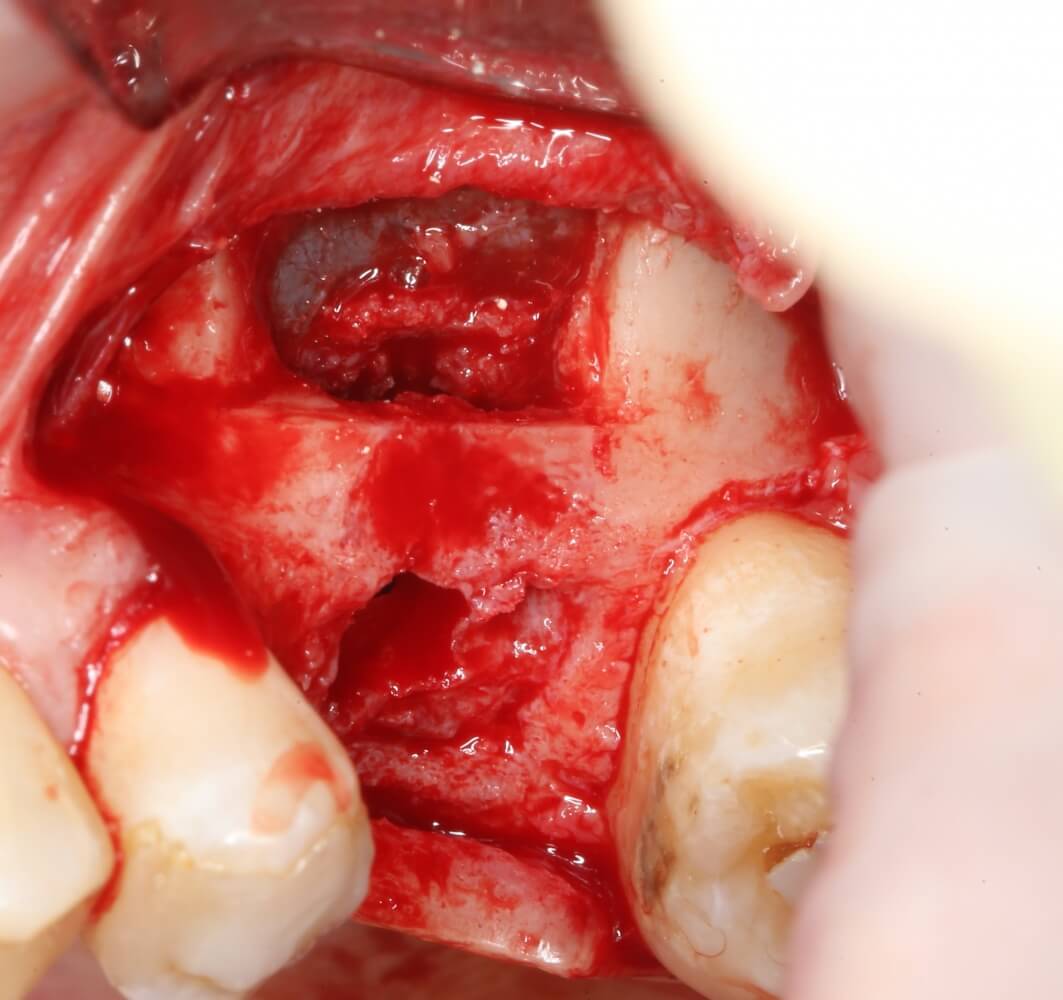

Начинаем подготовку лунки под имплантат

Далее, мы проходим лунку на всю глубину пилотной фрезой диаметром 2.0 мм.

Следующей мы используем фрезу 2.0/3.2:

Такие фрезы — особенность имплантационной системы Astra Tech. Они нужны для того, чтобы не разломать края лунки и сделать переход между фрезами (а мы переходим с 2.0 на 3.2 мм) более точным и плавным, благодаря направляющей 2.0 мм. Однако, пройти лунку такой фрезой на всю глубину удаётся далеко не всегда. В таких случаях используется обычная спиральная фреза диаметром 3.2 мм (с зеленой полоской). Но в нашем случае такой необходимости нет, ибо выше только субантральное пространство, поэтому мы работаем только вот такой двойной фрезой.